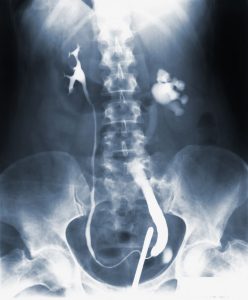

Røntgenundersøgelse